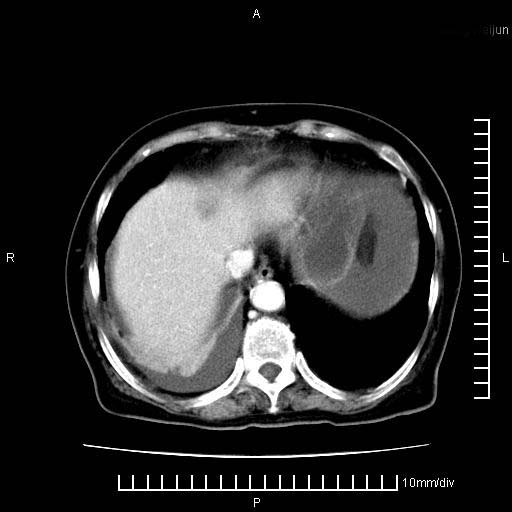

标题: CT28280:腹部增强:女性,80岁

上腹疼痛月余,外院核磁诊断胰腺癌。现临床示右下腹可明显触及包块,可片子上怎么没有看到?

1.胰腺颈体部癌。

2。腹腔积液。

3。右胸腔积液,伴右肺下叶部分萎陷。

4。右肾盂囊肿。

1。胰腺ca伴腹膜腔转移

2。肝左叶低密度灶,考虑转移可能

胰腺结构模糊,胰尾部见囊性包块,周围脂肪密度增高,左肾前筋膜增厚,胸水、腹水。不符合胰腺ca伴腹膜腔转移。考虑胰腺炎伴假性囊肿形成、胸腹腔积液。

右肾盂囊肿。

1)考虑胰腺癌并胰腺假性囊肿形成。2)肝内低密度灶,不排除转移。3)右肾盂积水。4)腹水。5)右侧胸腔积液并右肺下叶部分膨胀不全。

考虑胰腺ca伴腹膜腔转移、肝左叶转移、右肾积水。右胸腔积液。